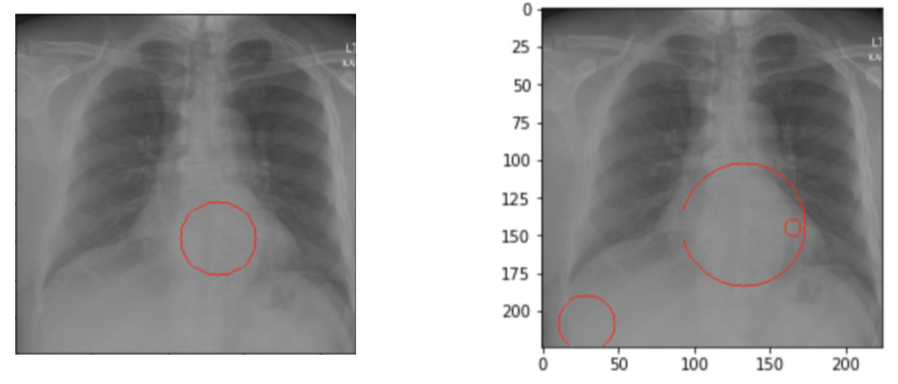

We address this issue by introducing a tuning parameter called sight sensitivity. Treating the image as a 2-D grid, this algorithm treats positive signals as points on a plane. These signals are obtained via the integrated gradients. These partial gradients of the image yield the influence of each pixel on the resulting classification decision. A large partial gradient value of a pixel is regarded as a positive signal. The sight sensitivity parameter is the threshold value which decides if a given gradient is large enough to be considered as a signal or not.

This parameter can be tuned to yield signal points on the 2-D grid. All other pixel gradients that fail to surpass this threshold are turned off (0 values). The remaining points are clustered in an unsupervised manner. Based on information loss criteria of distance, the points are clustered around their anomaly neighborhoods. The centroids of these clusters act as the center of the circles drawn around these bounding circles. The radius of the bound is equal to the farthest away point’s distance to its cluster’s center point.

Above methodology is depicted in Figure 2. The ground truth for the patient is: ”There are degenerative changes in the spine. Borderline enlarged heart.”. The detection in the low sight sensitivity setting (bottom right) lets too much signal pass through. The result of this is detailed bounds around the spinal area and with an emphasis on the heart, accompanied with noise on the bottom left portion of the image. The higher sight sensitivity (bottom left) produces an averaged out explanation without the structured noise by trading off some true positive signals.